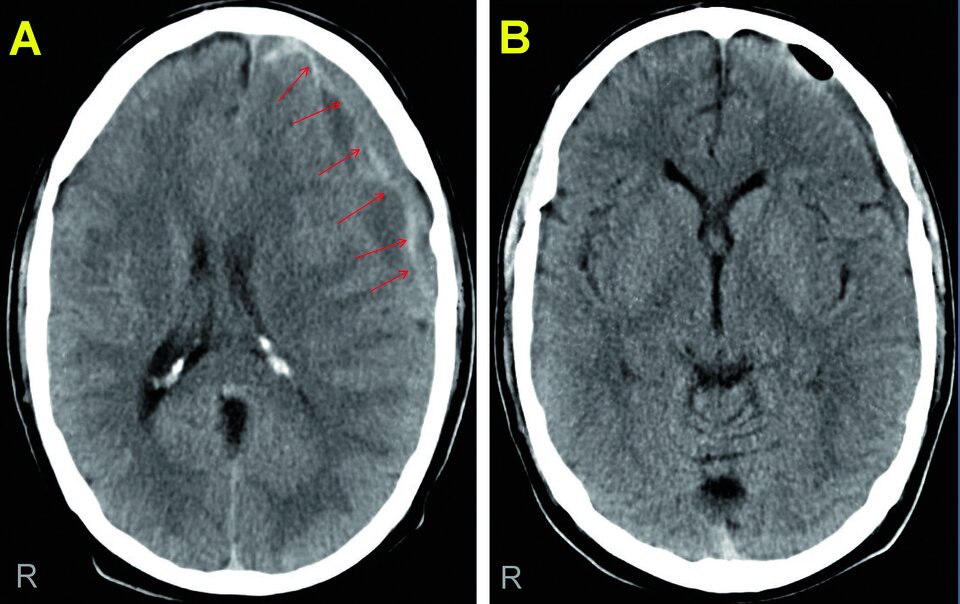

Die kraniale Computertomografie zeigte ein chronisches Subduralhämatom links frontotemporal (s. Abb. 1). In der präoperativen Gerinnungsdiagnostik fand sich passend zur Medikamentenanamnese eine aufgehobene Thrombozytenfunktion. Durch eine Bohrlochtrepanation gelang es, das Hämatom vollständig zu entleeren. Nach wenigen Tagen war der Patient wieder beschwerdefrei.

Abb.1: Chronisches Subduralhämatom (Pfeile) mit Verdrängung der Mittellinie nach rechts (A). Die Bohrlochtrepanation  führte zu einer vollständigen Entleerung, die Falx cerebri ist wieder mittelständig (B). Abb.1: Chronisches Subduralhämatom (Pfeile) mit Verdrängung der Mittellinie nach rechts (A). Die Bohrlochtrepanation führte zu einer vollständigen Entleerung, die Falx cerebri ist wieder mittelständig (B). © Schulz C et al. Wehrmedizinische Monatsschrift 2022; 66: 214-223; DOI: 10.48701/opus4-21 © Beta Verlag & Marketinggesellschaft mbH, Bonn